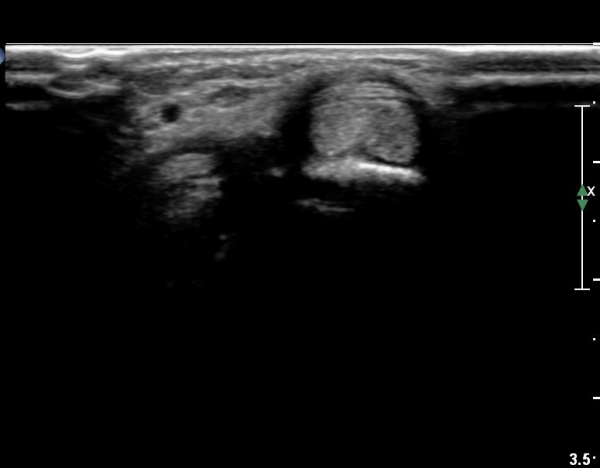

¿ä°ñ ¸»´Ü lister's tubercle ºÎÀ§¿¡¼­ Àå, ´Ü¿äÃø¼ö±Ù½ÅÀü°Ç Ⱦ´Ü¸é°Ë»ç¿¡¼­ ƯÀÌ ¼Ò°ßÀ» º¸ÀÌÁö

¾Ê´Â´Ù(»çÁø 3).